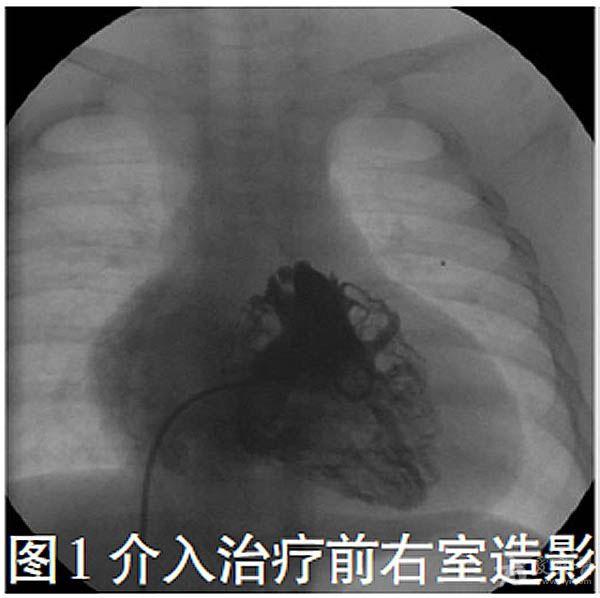

右心室流出道呈管型,肺动脉膜性闭锁(图1,主肺动脉发育正常,肺动脉